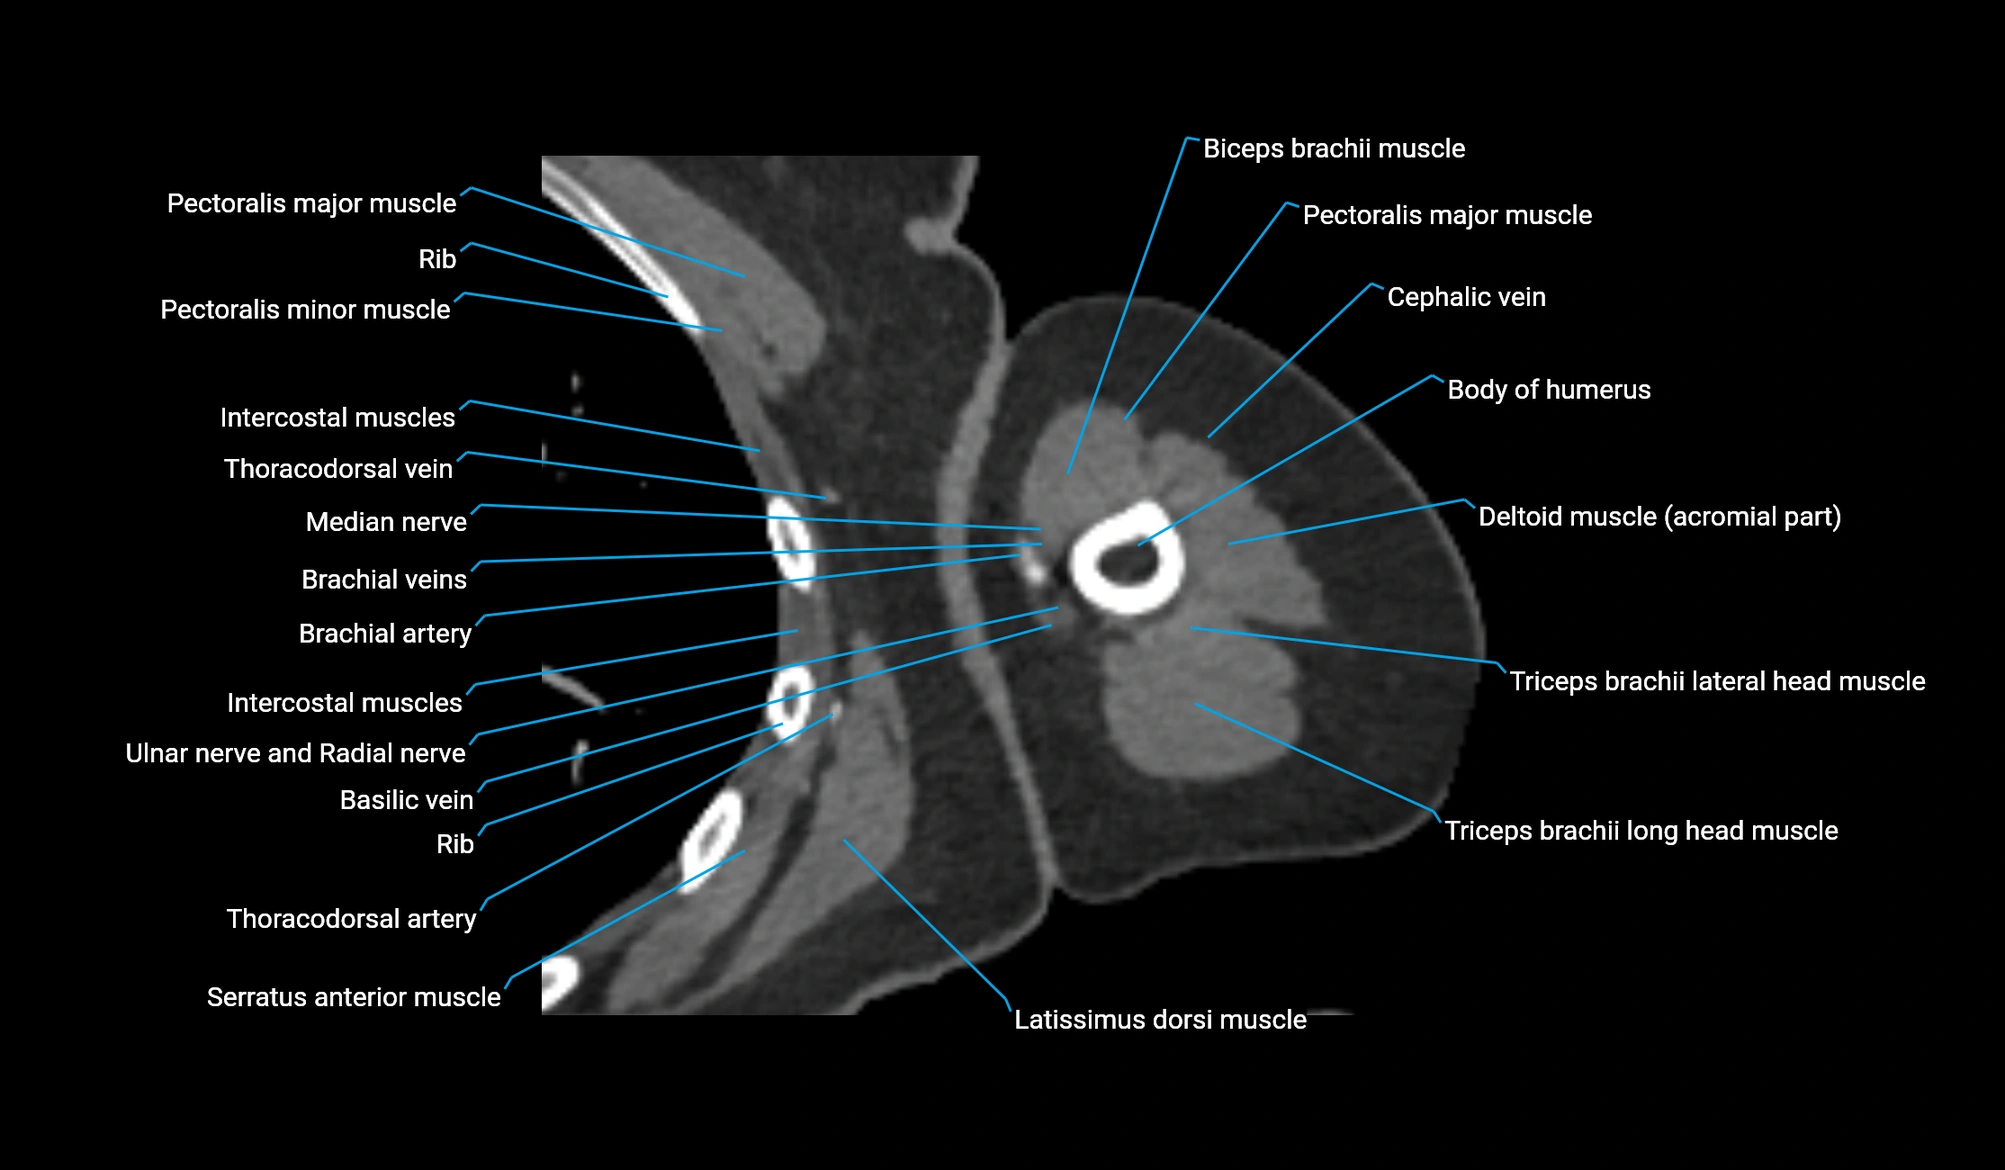

CT image